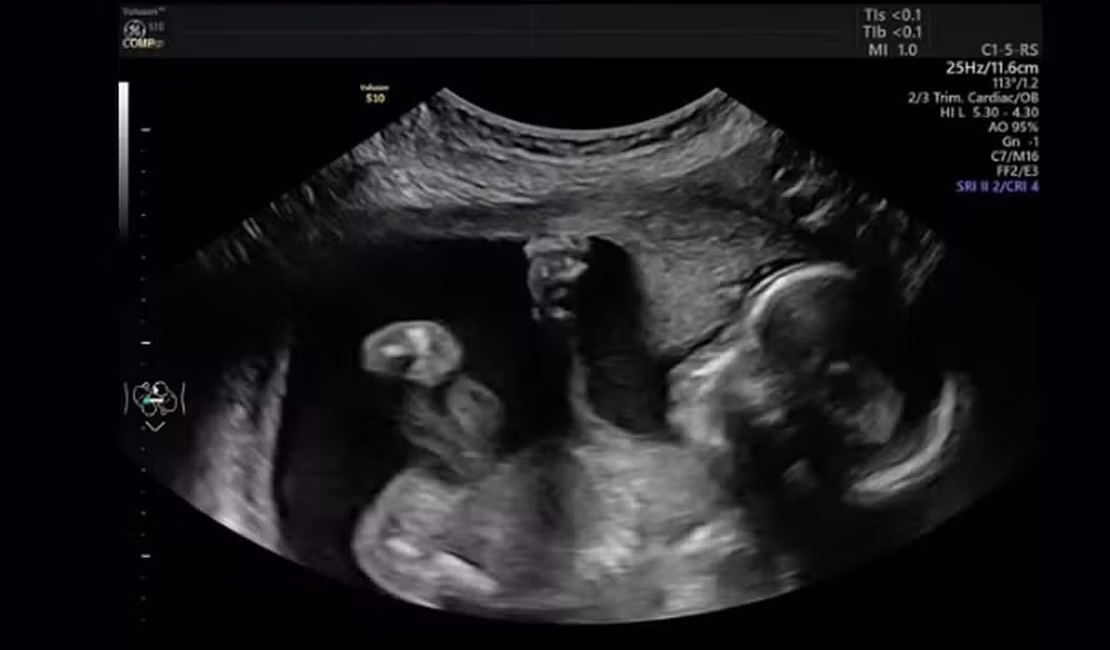

O consultório médico em Michigan (EUA) explodiu em gargalhadas quando Mara McCoy estava sendo submetida a um exame de ultrassom na 20ª semana de gravidez, em setembro.

A cena pegou a todos de surpresa. Tudo transcorria normalmente até que Pyper resolveu se manifestar: a bebê foi vista "dando um soco" na barriga da mãe. A cena, capturada pelo pai, Terrance McCoy, parecia mostrar que a pequena estava se sentindo incomodada com o exame.

"O vídeo mostra o quão brava ela é", disse a mãe. "Ela estava muito ativa e pareceu me dar um soco. Ela pode ser a próxima Ronda Rousey", continuou ela, referindo-se a uma famosa atleta de MMA.

Embora o soco possa ter parecido "pessoal", os médicos dizem que movimentos fetais como golpes com as mãos, chutes e alongamentos são completamente normais nessa fase da gestação.